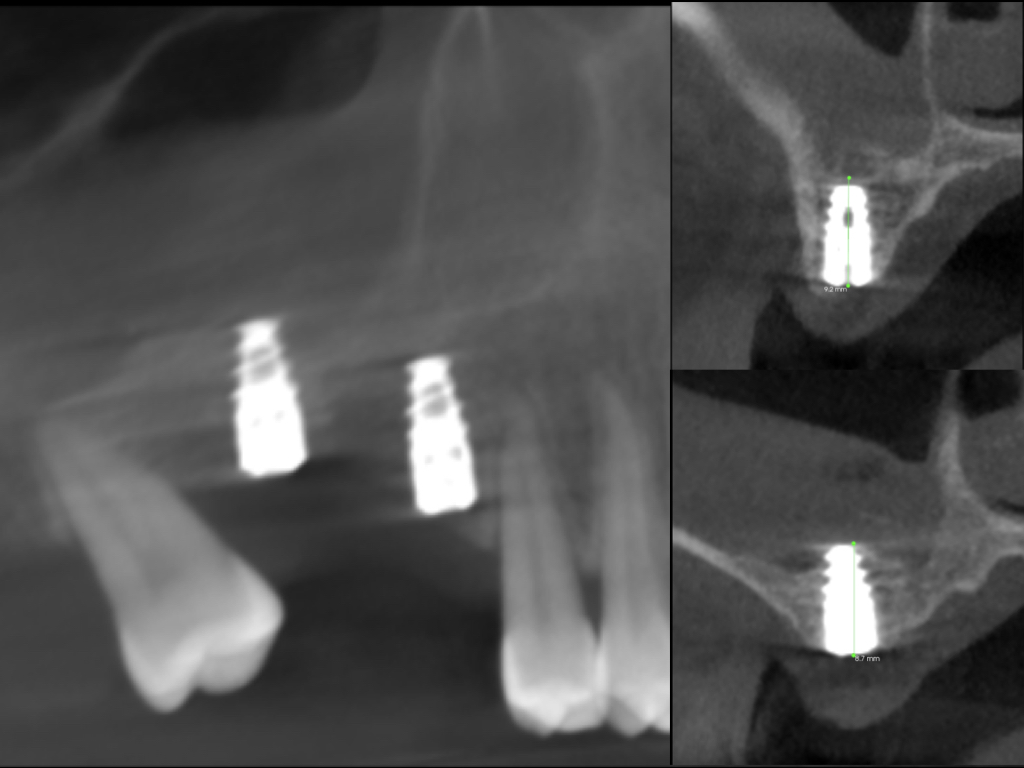

Material y método: la población estudiada son 24 pacientes, 16 de sexo femenino (66,6%), y 8 de sexo masculino (33,33%), con edades comprendidas entre los 12 y 15 años, que presentaron un valor del ángulo ANB de clase II (ángulo formado por el punto A – punto Na – punto B). Se utilizaron las telerradiografías laterales de cráneo iniciales y finales del mencionado grupo, habiéndose creado un método específico de 26 medidas para realizar la investigación.

Resultados: en los resultados obtenidos de la muestra se ha observado un claro aumento de los valores del crecimiento mandibular, tanto verticales como horizontales, como los valores que evalúan la posición sagital horizontal de los dientes inferiores del grupo estudiado.